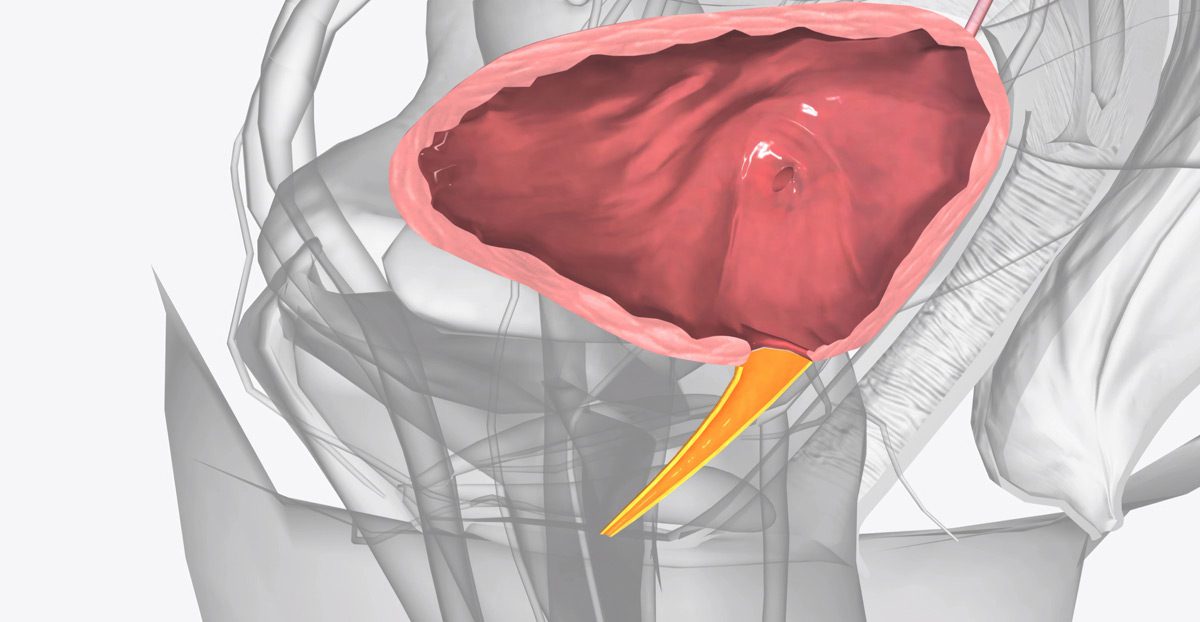

The AUS is a mechanical device implanted inside the body to control the flow of urine. It mimics the function of a healthy sphincter by keeping the urethra closed until the patient is ready to urinate. The system consists of three components:

- Cuff: Placed around the urethra to keep it closed and prevent leakage

- Balloon Reservoir: Usually placed in the abdomen, helping regulate cuff pressure